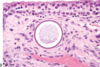

Respiratory disease of equids that causes transient broncho-interstitial pnumonia. Histological appearance shows foamy eosinophilic proteinaceous material within alveoli

Equine Adenovirus